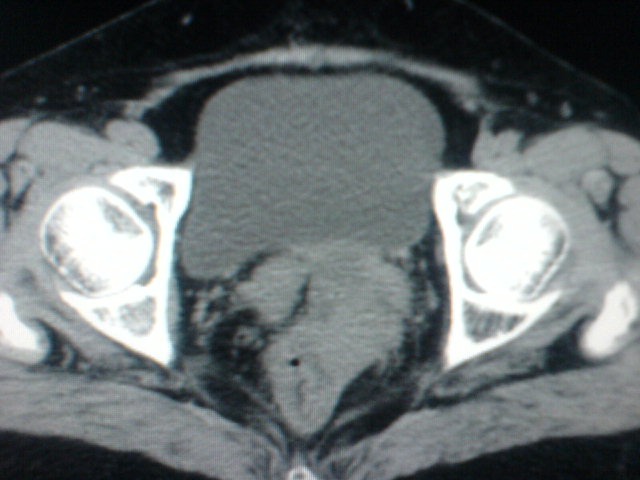

患者为老年女性,肿块最大层面不是位于宫颈,但宫颈偏后方有一囊状低密度影,肿块主要位于乙状结肠及直肠,所以考虑乙状结肠及直肠癌浸犯宫颈可能性大。

患者女性60岁 病史不详

宫颈癌侵犯直肠可能

考虑子宫内膜癌浸犯直肠。

考虑直肠癌侵及宫颈可能;建议增强扫描。

支持考虑宫颈癌上下前后通吃

考虑:直肠及乙状结肠癌侵及宫颈,囊性转移(假性粘液瘤)

支持宫颈癌侵犯直肠。

考虑直肠及乙状结肠癌侵犯邻近结构。